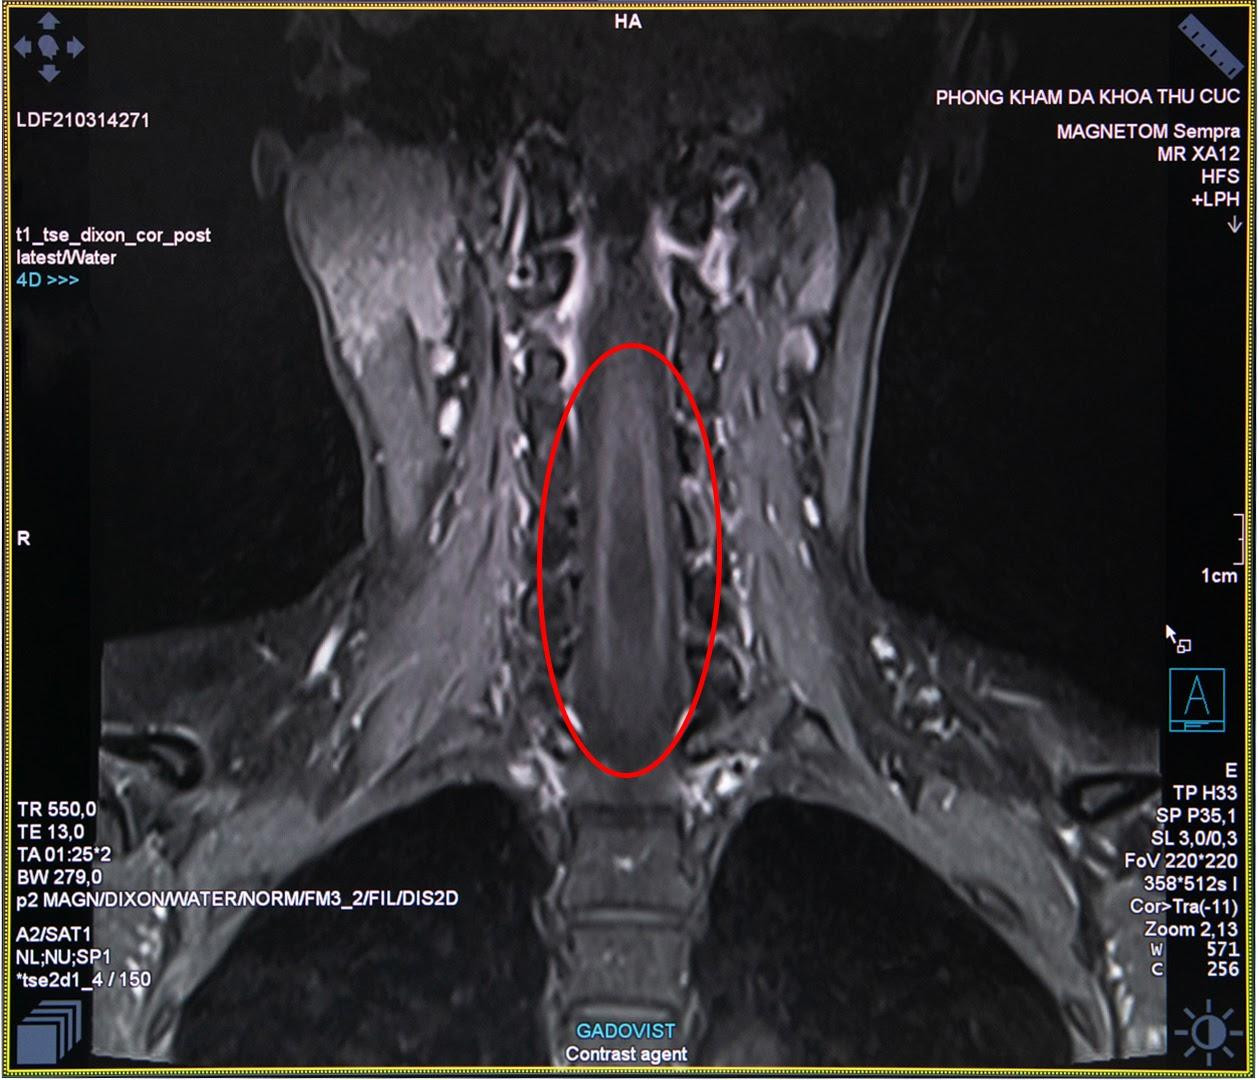

Bác sĩ chẩn đoán hình ảnh Nguyễn Chí Phồn - Phòng khám đa khoa Thu Cúc cho biết: “Trường hợp của chị H. là chụp cộng hưởng tử MRI cột sống và tuỷ sống có tiêm thuốc đối quang từ nhằm phát hiện những tổn thương thần kinh. Đây là công cụ đáng tin cậy nhất để chẩn đoán bệnh rỗng tuỷ sống. Đối với những trường hợp nghi ngờ bệnh nhân bị rỗng tủy sống nếu chỉ định chụp X- Quang hay chụp cắt lớp vi tính MSCT sẽ khó có thể đánh giá chính xác được”.

Hình ảnh thu được từ chụp cộng hưởng từ MRI tủy sống của chị H. cho thấy trong đoạn tủy sống của chị hình thành một hốc rỗng chứa các dịch, các dịch này tích lại thành các khoang và nang hốc đây là biểu hiện của căn bệnh rỗng tủy. Ngay sau khi có kết quả khám cận lâm sàng, các bác sĩ của Thu Cúc đã hội chẩn nhằm xác định căn nguyên bệnh và tìm ra phương pháp điều trị tốt nhất cho chị H.